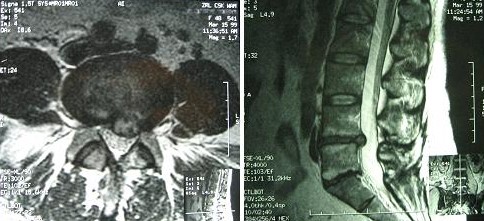

Badanie obrazowe przedstawia:

Pytanie 84

Do oddziału rehabilitacji przyjęto chorego lat 21 z rozpoznanym niedowładem kończyn dolnych bez zaburzeń w oddawaniu moczu po urazowym zwichnięciu kręgosłupa na poziomie Th12-L1 dwa tygodnie temu. Wykonano badanie przeglądowe kręgosłupa, które pokazane jest poniżej.

Pytanie 86